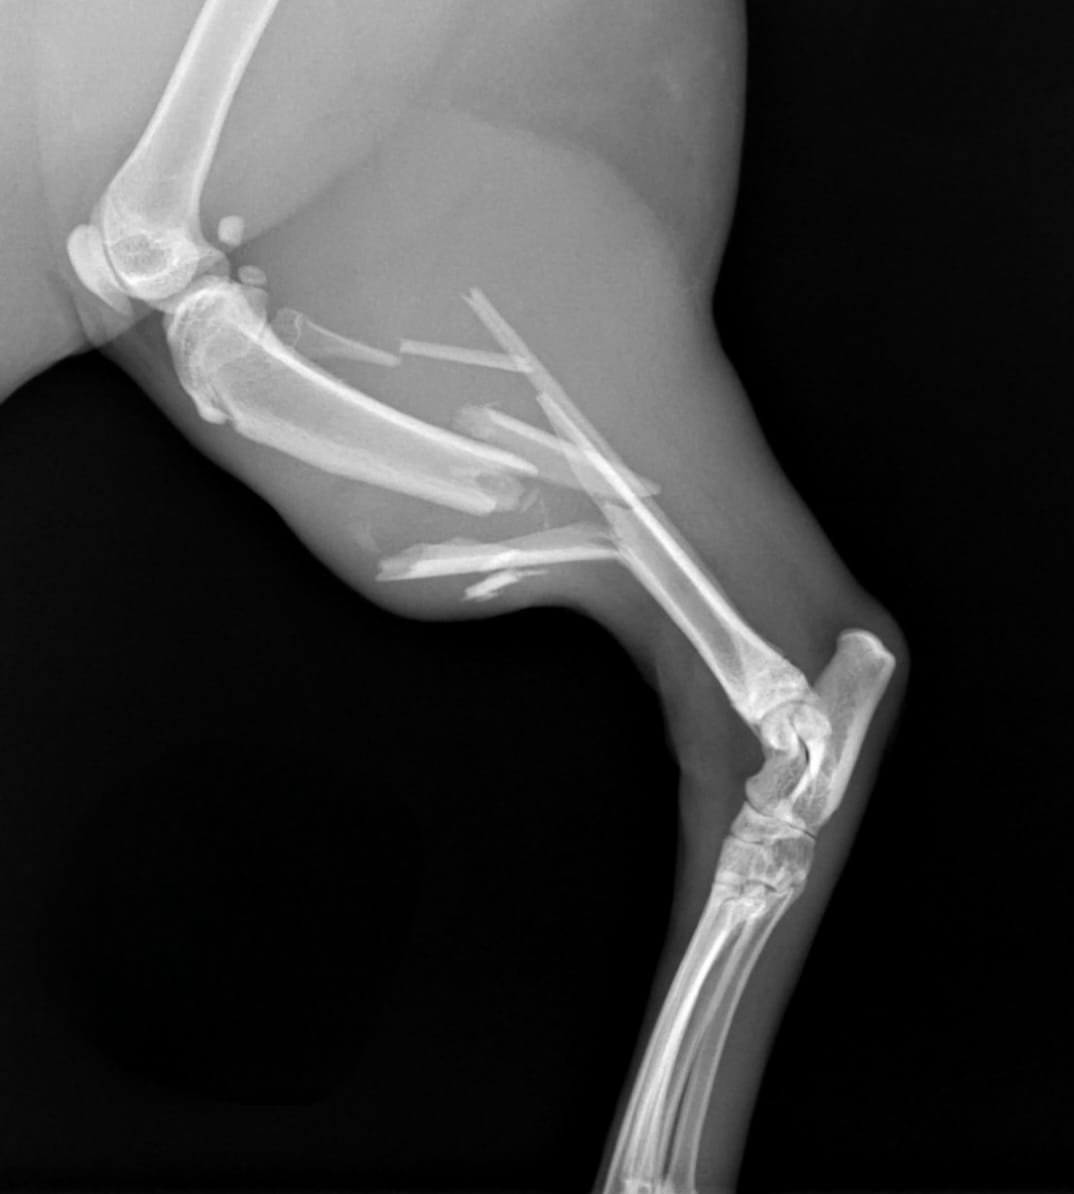

Comminuted tibial fracture in a cat

Male, 1 years old, 5 kg domestic short hair

presented with acute 4 grade right hindlimb lameness

reported trauma 10 days ago after falling down from 3rd floor

Referring veterinarian performed chest and abdominal x-ray that detect minimal lung contusion without further damage to internal organs. Blood work (cbc, biochemistry) did not detect any abnormalities. 10 days after the trauma patient was admitted to surgery.

Radiographic exam reveal complete closed comminuted mid-diaphyseal tibial fracture, with severe displacement of fragments.